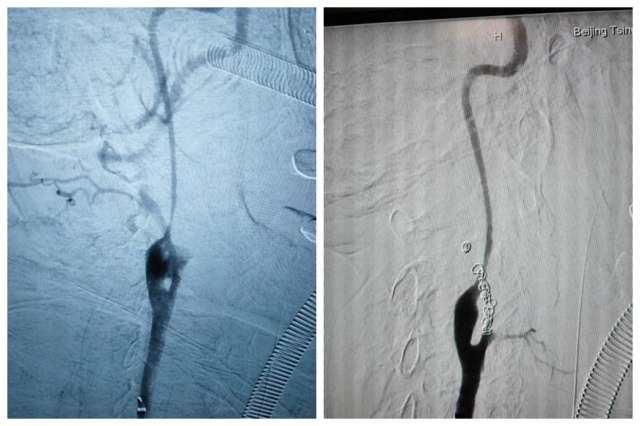

动脉造影可见颈外动脉造影剂外溢,栓塞后止血

患者从急诊紧急接入手术室,就在此时,患者突发心脏骤停,血管外科、麻醉科、耳鼻咽喉头颈外科医师齐上阵,立即对患者实施抢救,三名医师轮流为患者进行心肺复苏数轮,患者逐渐恢复了自主心律。在麻醉科的保障下,血管外科曹战江、蒋超、李子澎医师联合手术,行颈总动脉穿刺,造影可见颈外动脉被肿瘤侵犯破裂出血,行动脉栓塞后,出血最终止住,患者血压同步恢复稳定,转至重症监护病房。